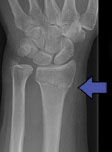

Also referred to as Colles’ or Smith’s fracture, Broken Wrist – Distal Radial Fracture is often associated with the shortening of the radius. If the fracture occurs close to the wrist, this can alter the alignment of the joint, causing pain and loss of function.

See below the two treatment approaches for a patient who has broken wrist.

Colles’ Fracture or a Broken Wrist is complex and can lead to serious complications and frustrations if not treated appropriately.

Your Hand Therapist, Physiotherapist or Occupational Therapist at Action Rehab will assess your X-rays, educate you on the injury and then fabricate the right brace for you. The therapists at Action Rehab are experienced in assessing and reading X-rays.

Colles’ Fracture or a Broken wrist is the most common fracture of the arm or wrist. A Broken Wrist or Colles’ Fracture is most common in women over 50 years of age.

Broken wrist is caused by a fall on an outstretched hand. It is common in ball sports such as tennis.

Colles’ Fracture or a Broken wrist takes about 6-8 weeks to recover but depending on the type of injury it may take longer. Surgery doesn’t normally make the process faster but it will help to stabilise an otherwise unstable fracture.

Surgery is often indicated following a Colles’ Fracture or a Broken Wrist but careful assessment is required. Action Rehab therapists can assess the X-ray and can advise if your Broken Wrist injury needs surgery.